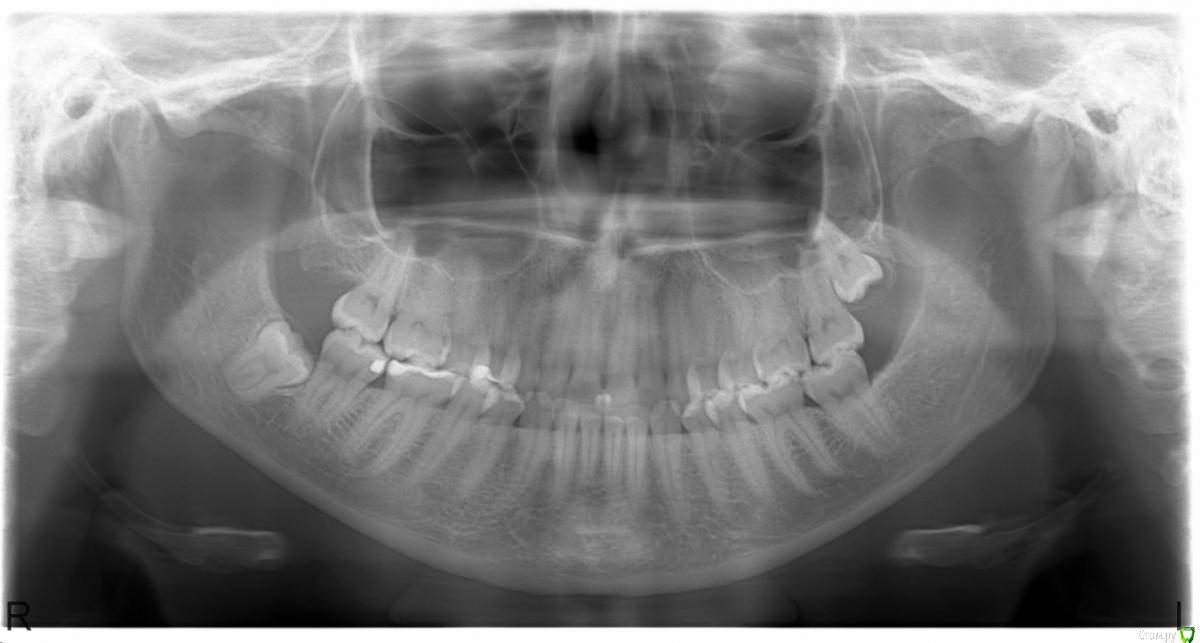

kadetlessy Опубликовано 28 ноября, 2019 Поделиться Опубликовано 28 ноября, 2019 (изменено) Здравствуйте! Дайте, пожалуйста, совет по поводу удаления нижней восьмерки. Снимок прилагаю. Была у двух специалистов. Один берется удалять без проблем, второй отказывается удалять, говорит, что зуб в кости, что это операция в стационаре и он не будет заниматься вредительством. Есть боль наверху неясной локализации, поэтому задумалась об удалении этого зуба, как о потенциальном источнике боли. Изменено 28 ноября, 2019 пользователем kadetlessy Ссылка на комментарий

red_butler Опубликовано 28 ноября, 2019 Поделиться Опубликовано 28 ноября, 2019 Не вижу проблем с удалением. Ищите квалифицированного хирург 1 Ссылка на комментарий

Jurai Опубликовано 28 ноября, 2019 Поделиться Опубликовано 28 ноября, 2019 Идите к первому специалисту, который не видит проблемы с удалением) удалять нужно и нижнюю справа и верхнюю слева. 1 Ссылка на комментарий